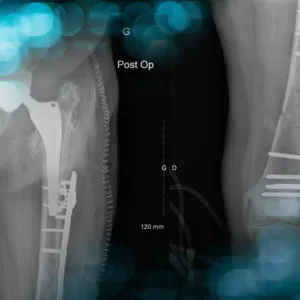

This clinical case describes the management of a 69-year-old man who sustained an acetabular fracture after a bicycle fall. His treatment was complicated by a massive pulmonary embolism, preventing immediate surgical intervention.